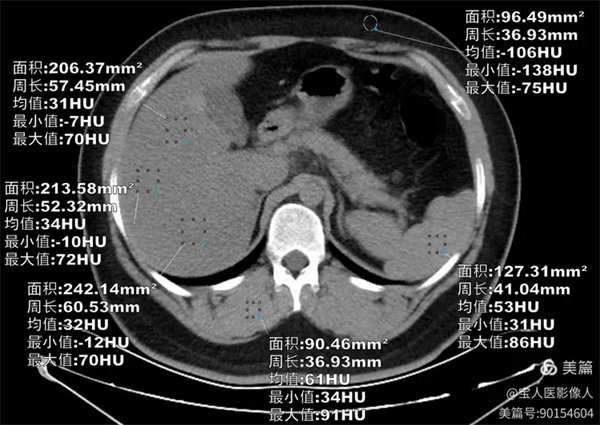

圖1

CT軸位,肝形態,大小正常,CT值最低約31HU,較正常肝實質密度降低。